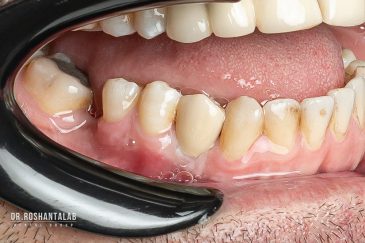

🔸 کاشت دندان یک روزه ( کشیدن و کاشت همزمان )

🔸 ایمپلنت دیجیتال و ساخت روکش دیجیتال

تجربه کاشت دندان دیجیتال و بدون درد در ۳ دقیقه! استفاده از برترین برندها زیر نظر جراح، با هزینه مناسب و خدمات کامل از کاشت دندان تا روکشارتودنسی دندان